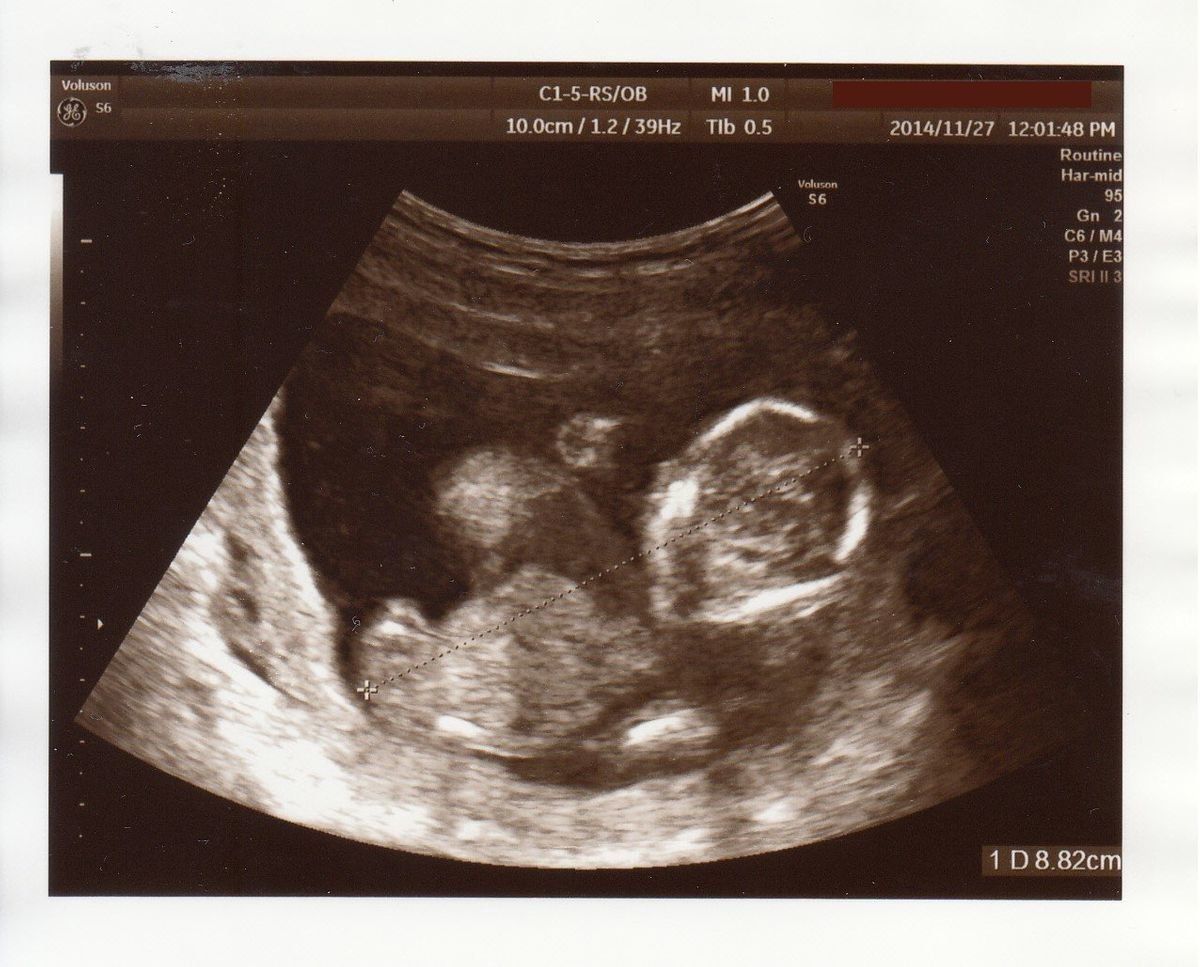

転院することに - 妊娠33週目のエコー写真

エコー写真は、ちょっとわかりにくいですが右側が頭、左側がお尻です。少しくびれたところが首、真ん中上下に腕が伸びています。左側、お尻の上下に足が見えます。赤ちゃんの推定体重は1735g。標準値を下回ってしまいました。何らかの原因で赤ちゃんの育ちが悪いと診断され、大きな病院への転院が決まります。とても動揺して、ネットで赤ちゃんの育ちが悪い原因を調べるなど、不安が消えない日々を過ごしました。

家から徒歩5分の産院から、車で1時間ほどの大学病院に転院することになりました。3ヶ所の大きな病院から選ぶように言われ、なんとなく車で行きやすそうなところに決めました。結婚で引っ越してきた土地なので、病院の情報や土地勘がありません。今思えば、一度持ち帰って、きちんと検討すればよかったと少し後悔しています。